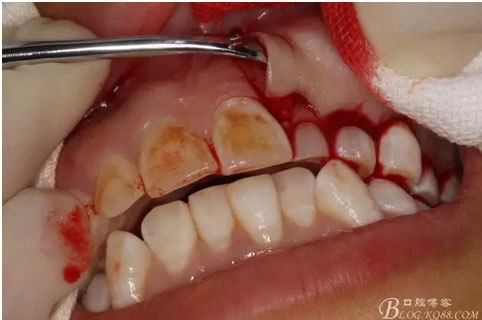

圖9.從兩個切口的連接處開始翻瓣。全厚瓣。

圖10.暴露出骨性隆起。骨質表面光滑。

圖11.暴露出23的牙尖,牙尖垂直于唇側粘膜。建議拔除,患者同意。